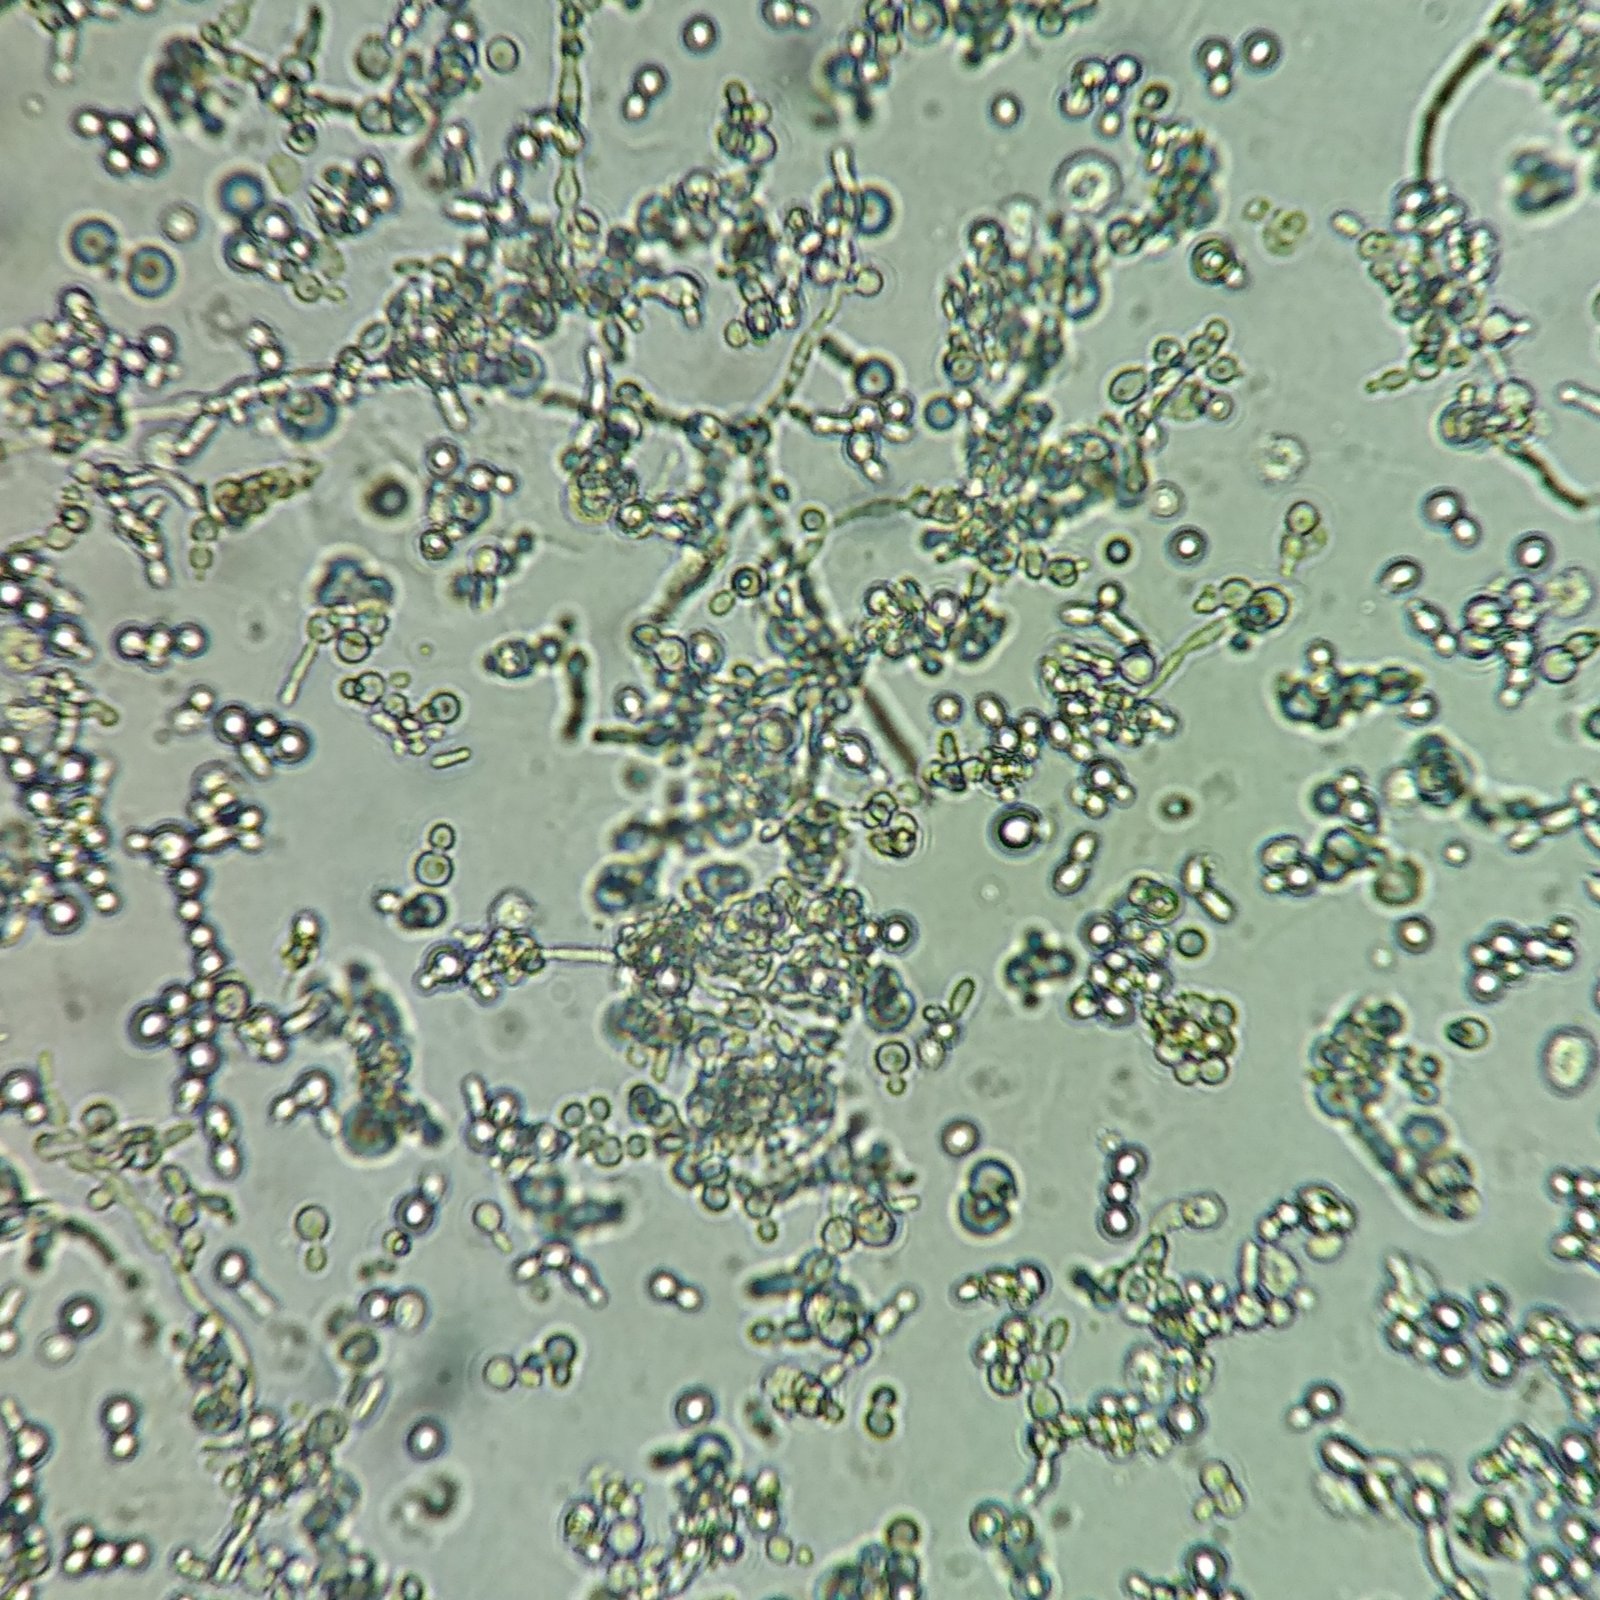

Appearance

Trichomonas are pear-shaped and have four flagella. Motility is usually necessary for identification.

Trichomonas can look like a white blood cell when non-motile which is why motility is usually necessary to positively identify by microscopy.